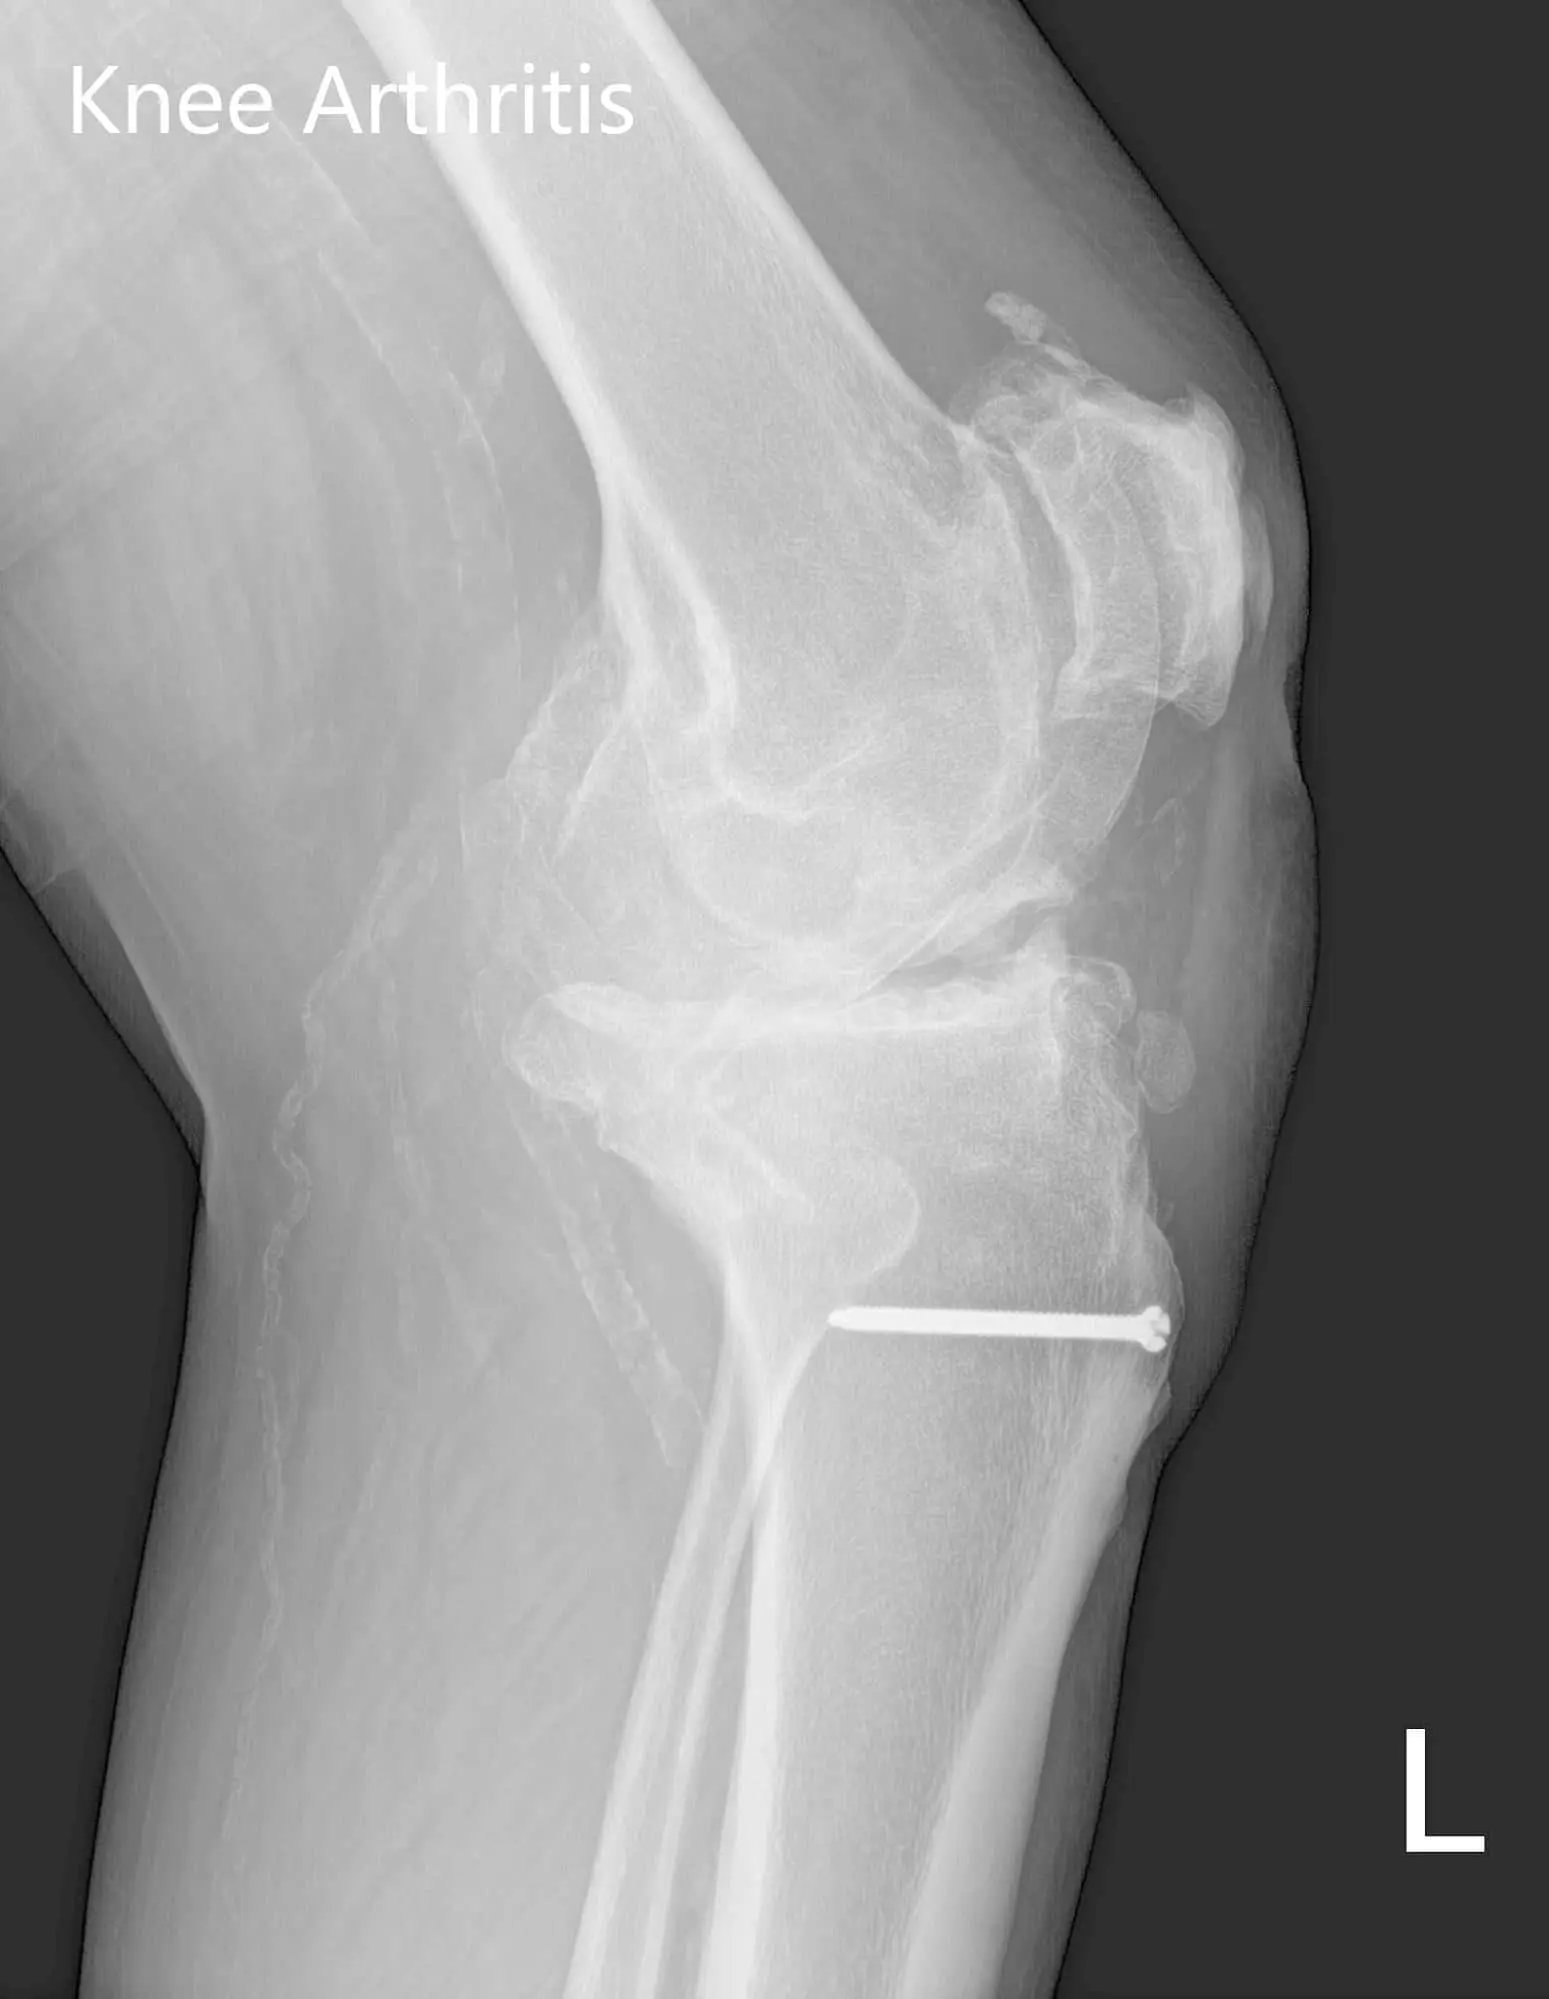

The patient’s physical examination revealed a horizontal scar over the left tibial tubercle. There was mild swelling with genu varus and flexion deformity. The range of motion of the left knee was found to be 10-95 degrees. Medial joint line and medial patellar facet tenderness were elicited. The patient was visibly under distress due to pain. She stated she wanted to explore the options of knee arthroplasty.

Her imaging studies revealed tricompartmental osteoarthritis of the left knee with a retained hardware (bolt) in the left proximal tibia. After assessing her medical conditions and physical examination she was deemed as a candidate for custom knee replacement. She was advised to undergo only the left side in view of the previous history of myocardial infraction and then proceed for right knee.

Preoperative X-ray of the left knee showing AP and lateral views with degenerative osteoarthritic changes and retained hardware in the proximal tibiaPreoperative X-ray of the left knee showing AP and lateral views with degenerative osteoarthritic changes and retained hardware in the proximal tibia - img 2

Preoperative X-ray of the left knee showing AP and lateral views with degenerative osteoarthritic changes and retained hardware in the proximal tibia.